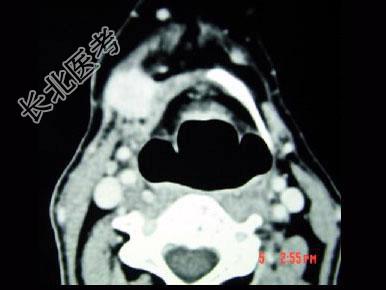

- 单项选择题男,45岁, 右侧颌下扪及一包块约4个月,无痛, PE:包块质硬, 表面欠光整,移动度较差, CT如图所示,最可能的诊断是 ( )